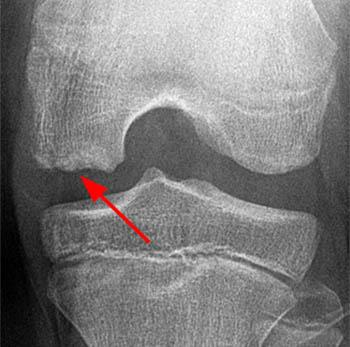

Diz eklem kıkırdağında hasarlanma

Kıkırdak yaralanmalarının tanısı için öncelikle hastanın şikayeti ve hikayesi öğrenilir. Sonrasında ayrıntılı bir muayene yapılır ve gerekirse röntgen, MRG, MR-artrografi ve artroskopi gibi görüntüleme yöntemlerine başvurulur.

| Eklem kıkırdağında bozulma olan dizin; A. Röntgen filmi, B. MR görüntüsü |